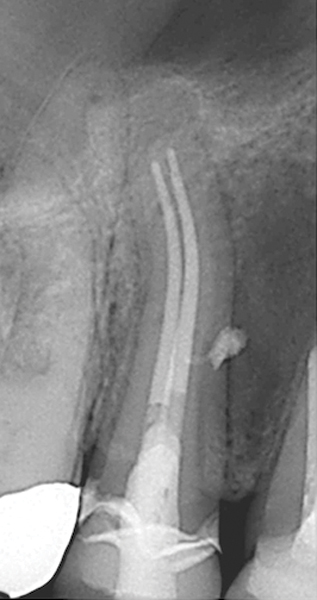

Figure 15. Preoperative radiograph. Courtesy of Dr. Sam Kratchman.

Figure 15

Figure 16. Post apicoectomy. Courtesy of Dr. Sam Kratchman.

Figure 16

Figure 17. Retropreps and isthus filled. Courtesy of Dr. Sam Kratchman.

Figure 17

Case 3: Apicoectomy and Retrofill

A patient presented with clinical symptoms and radiographic signs of post-endodontic disease (Figure 15). It was determined that the ledge on the mesial canals precluded retreatment and that an apicoectomy was to be performed. After locating the apicoectomy, it was possible to visualize both canals and an obvious isthmus between the two main canals (Figure 16). Retro-preparations were performed in the main canals, and the isthmus between them was grooved and the cavities filled with BC RRM-Putty (Figure 17). At the 20-month follow-up, the patient was asymptomatic and the radiograph showed complete healing (Figure 18).